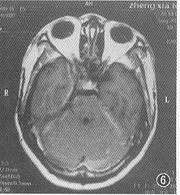

图6 1999年8月MRI横断面增强扫描示右侧海绵窦及颞叶下极增厚的硬脑膜不再强化,提示纤维结缔组织增生。右侧颈内动脉仍受压

出院7个月后,1998年4月,出现精神异常,时而安静,时而烦躁打骂亲人,曾送精神病院治疗未见好转。1998年5月13日来院复查。除精神症状外,一般情况良好。MRI颅脑横断面、冠状及矢状位扫描并增强显示:右中颅窝底硬脑膜、右侧小脑幕均见明显强化的带状影,右侧颞叶水肿,局部脑沟消失(图2);右侧脑室颞角受压变小(图3);右侧海绵窦影明显增大,增厚的窦壁使颈内动脉受压变细(图4)。根据MRI所见及临床症状确诊为弥漫性肥厚性硬脑膜炎伴右颞叶水肿及器质性精神障碍。每天青霉素静脉点滴10 000 000 U共26 d,临床症状消失。1999年8月28日(15个月后)复查 MRI,颞叶水肿消退,沟回重现,侧脑室颞角恢复正常(图5),肥厚的硬脑膜因已纤维化,故不再强化,但右侧颈内动脉仍受压(图6),2000年4月(23个月后)电话询问,患者工作、生活良好,并已成婚。

2.病理:本例岩锥处的硬脑膜肉眼检查未见特殊,穿刺岩上窦尚有血液回流。此种病变如作活体检查,一般可见增厚的硬脑膜中纤维结缔组织增生,其中胶原成分居多,伴有慢性炎细胞浸润。少数情况可见硬脑膜呈肉芽肿样增厚、坏死性肉芽肿、小脓肿、淋巴滤泡形成、中性粒细胞浸润及郎罕细胞等。总之,病因不同,肉眼检查及光镜所见亦异。对某些疑难病例,有时活体检查是唯一可靠的依据[3,11]。硬脑膜增厚,可以引起横窦、海绵窦及矢状窦等闭塞,本例海绵窦壁增厚引起颈内动脉不全闭塞,并曾有外展神经麻痹。文献报告有颈内动脉完全闭塞或C5、C6段颈内动脉严重狭窄者[3]。本例见硬脑膜广泛性增厚包围颞叶下极(图4,6),颞叶内曾有不规则大片水肿(图2~4)。